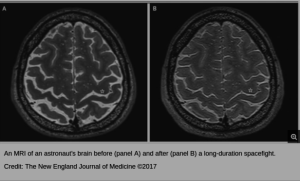

Researchers found both physical and chemical changes in the brains they examined, in addition to the behavioral changes they observed in the living mice……..